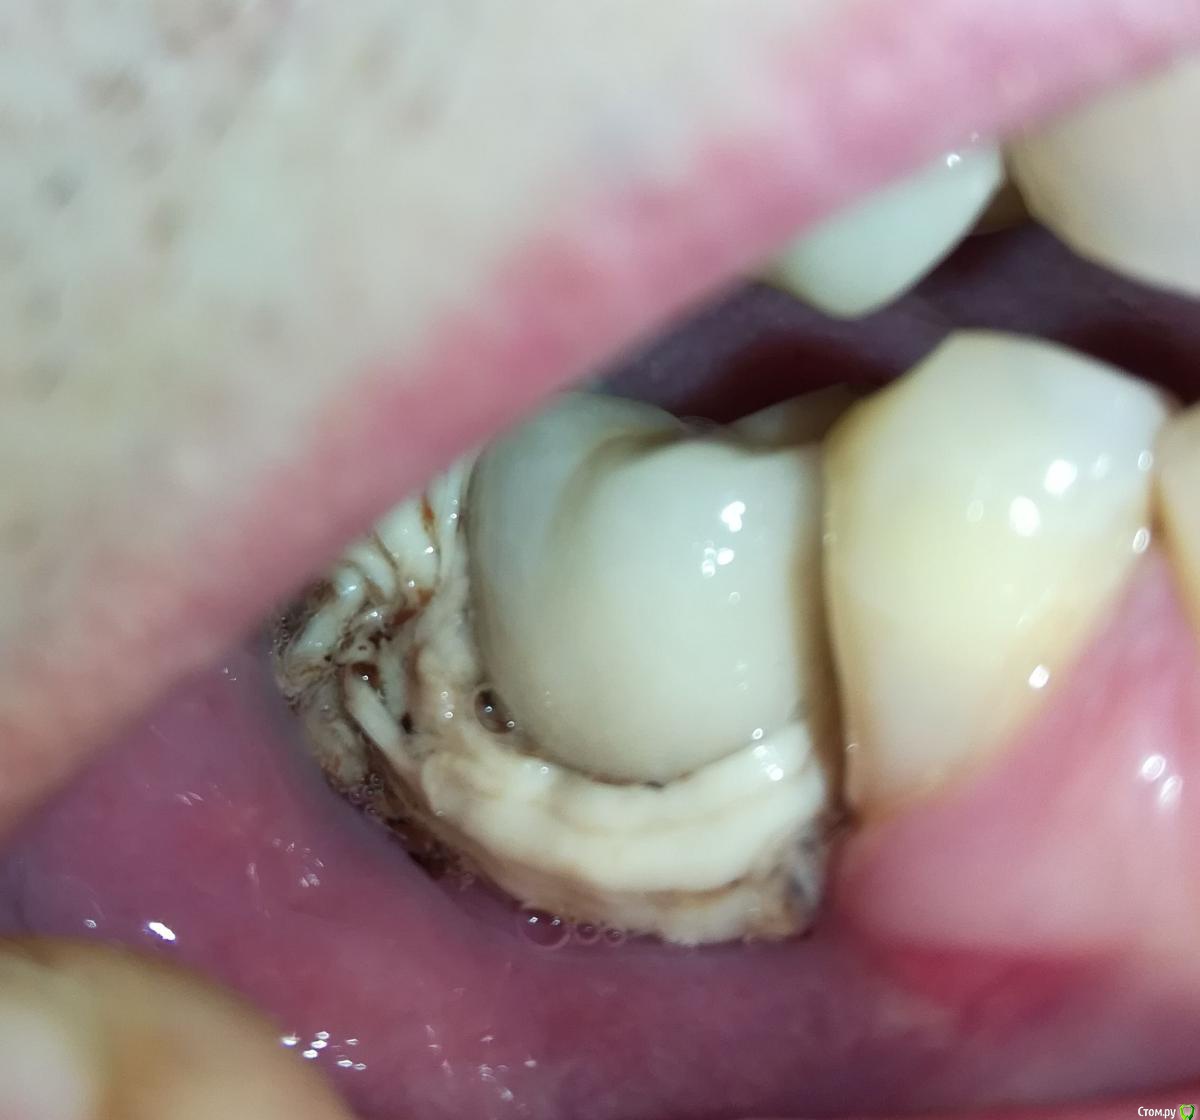

Alex19_73 Опубликовано 15 февраля, 2017 Поделиться Опубликовано 15 февраля, 2017 Доброго времени суток!Оцените пожалуйста качество имплантации и последующего протезирования. Имплантация проводилась с расщеплением гребня, имплант оказался смещен внутрь относительно других зубов. Хотел металлокерамическую коронку на винте, но ортопед сказал что возможно поставить только на цементе т.к. имплант сильно смещён внутрь. Вчера установили коронку но после дома стал разглядывать и она мне совсем не понравилась. По ощущениям очень неприятна, громоздка, когда жуешь то же как то не как родной зуб, языки щека постоянно по ней трут. С обратной стороны коронки обнаружил что то белое, наверно цемент, зубочисткой и ирригатором снять не удалось. Ортопед обратную поверхность зуба ковырял крюком счищая цемент. Это белое спускается с коронки прямо на десну.Можно ли если это цемент счистить его не испортив керамику коронки? Не может ли спровоцировать переимплантит такое затекание цемента, и вообще насколько это профессионально и соответствует протоколам (работа имплантолога и ортопеда)? Заранее спасибо. Ссылка на комментарий

M@estro Опубликовано 15 февраля, 2017 Поделиться Опубликовано 15 февраля, 2017 Здравствуйте! Это не цемент, так размоделирована коронка, насколько я могу судить по представленным фотографиям. Ссылка на комментарий

Alex19_73 Опубликовано 17 февраля, 2017 Автор Поделиться Опубликовано 17 февраля, 2017 К сожалению снимок после имплантации пока не делал, сразу после имплантации врач делал томографию, но она есть наверно только на компьютере в клинике. Перед протезированием имплант был в хорошем (насколько я могу судить) состоянии под нагрузкой проверяли. Был вчера у ортопеда, оказалось что это не цемент а коронка, просто если смотреть спереди низ кажется светлее. Что бы уменьшить застревание еды хирург предложил бесплатно сделать пластику десны, с чем я согласился. Коронку снять не удалось, несмотря на значительные усилия в течении часа . Цемент mis. Пластику решили делать с установленной коронкой. Спасибо ответившим. Ссылка на комментарий